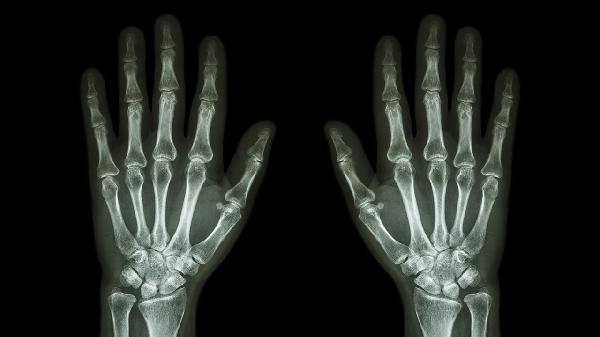

手指關(guān)節(jié)觸摸有刺痛感可能與關(guān)節(jié)勞損、骨關(guān)節(jié)炎、類風(fēng)濕關(guān)節(jié)炎、痛風(fēng)性關(guān)節(jié)炎或腕管綜合征等因素有關(guān)。刺痛感通常由局部炎癥、神經(jīng)壓迫或代謝異常引起,建議及時(shí)就醫(yī)明確病因。

日常應(yīng)注意保持手部溫暖,避免冷水刺激。進(jìn)行手指伸展操改善血液循環(huán),控制每日手機(jī)電腦使用時(shí)間。若刺痛持續(xù)超過兩周或伴隨關(guān)節(jié)變形、發(fā)熱等癥狀,須盡快至風(fēng)濕免疫科或骨科就診,完善X線、超聲或血液檢查。飲食上增加深海魚類攝入,補(bǔ)充歐米伽3脂肪酸有助于減輕炎癥反應(yīng)。